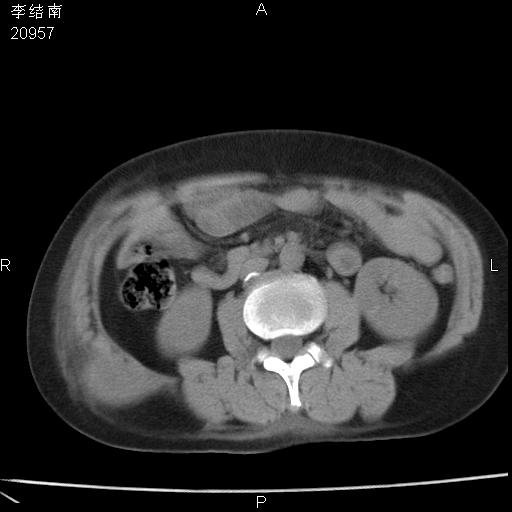

患者女,45岁,以右侧腰部包块来就诊,局部有压痛,皮肤颜色正常。因为是熟人扫的范围较大,患者有胆结石,胆源性胰腺炎病史。请大家看看,有手术病理。

可能大家觉得片子的质量不好,当时是做下腹部扫描,所以没有常规喝水,右腹壁的病灶当时是,密度不均有钙化影,局部骨质没见破坏,肝脏应该是受压的表现,所以当时考虑为腹壁的良性占位,各位老师考虑的神经源性肿瘤,我当时还真没想到,胰腺是胰腺炎治疗后改变.膈脚旁的混杂密度包快不好考虑什么,到上级医院做增强(腹部)+肺部平扫后,发现腹壁的病灶呈不均匀性强化局部可见囊性灶,当时考虑为腹壁结核,最具戏剧性的是膈脚旁的混杂密度灶确是胃的一部分,而腹壁的病灶确是脂肪瘤(简直不可思议)但是我亲眼所见在我们县医院开的.

很不好意思 ,患者后来手术切口裂开,临床医生作了病理证实是腹壁结核。

[病理诊断] CT13183腹壁结核!